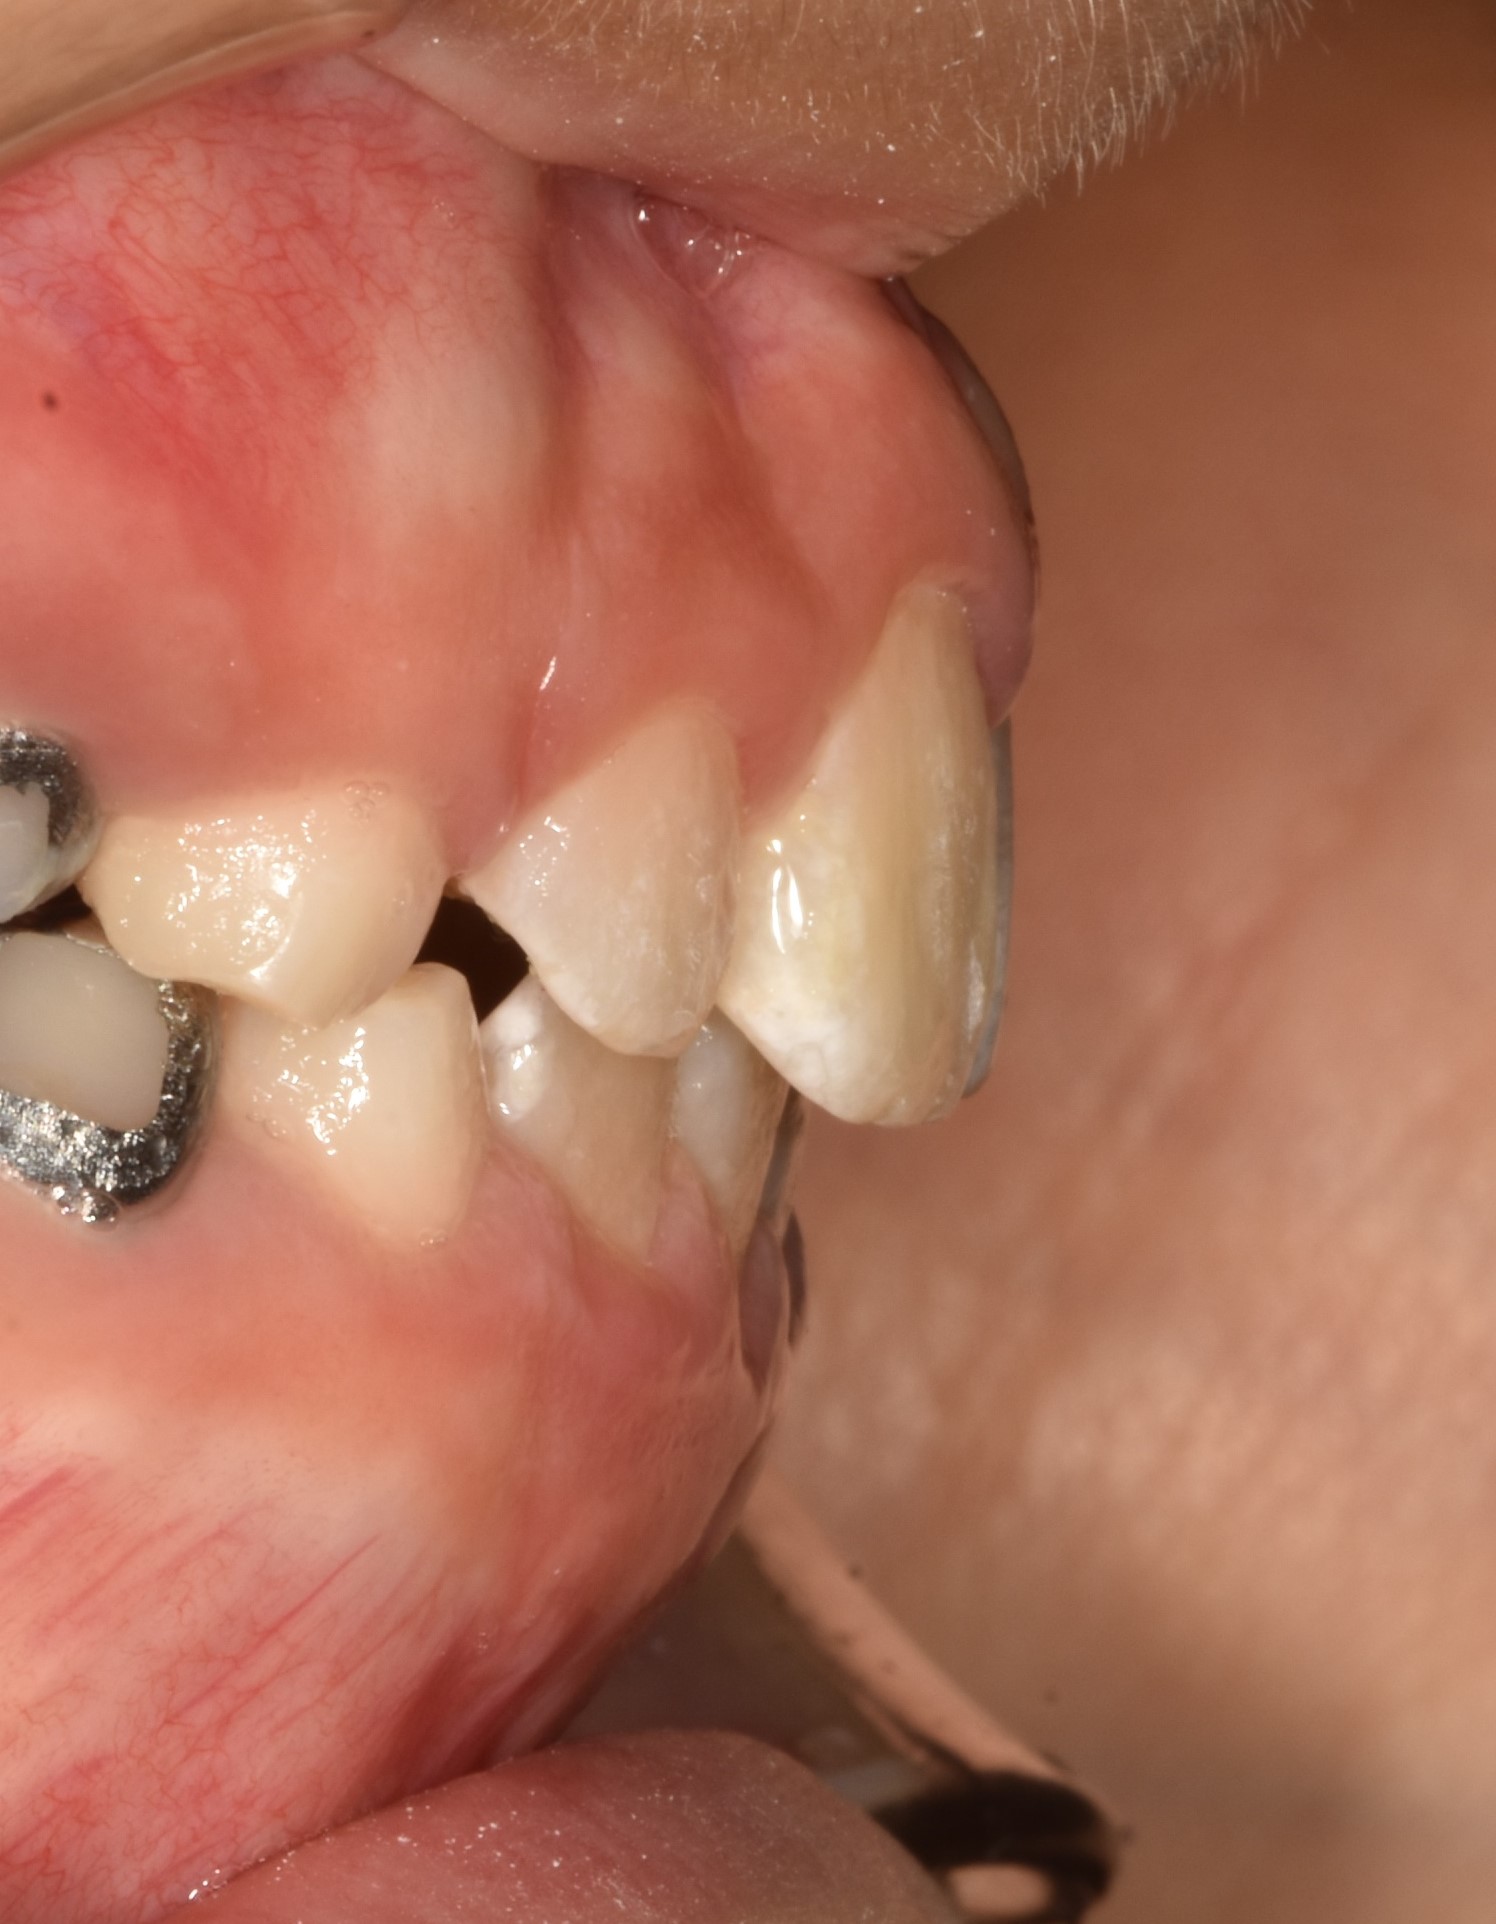

초진입니다. 위아래 앞나의 공간부족으로 이가 삐뚤뺴뚤 나고있고, 앞니도 뻐드려져있네요.